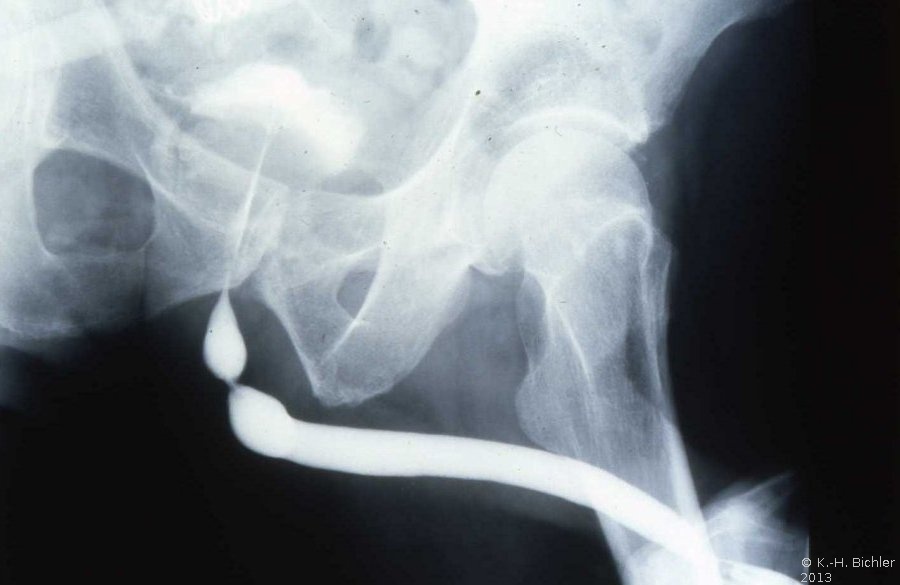

Sie sind Folge von Harnröhrenverletzungen, endourologischen Eingriffen bzw. Katheterisierungen, Entzündungen (Gonorrhoe) (Abbildung 15)

Diagnostik: Urinstatus, Uroflow, Urethrogramm